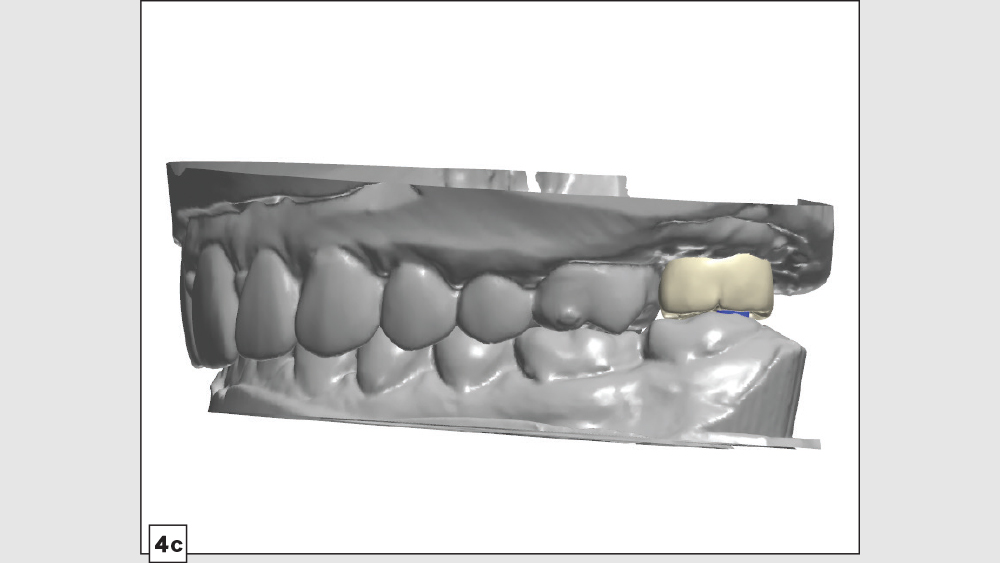

Now that we’ve explored the pros and cons of screw-retained and cementable implant restorations, let’s take a look at a unique clinical situation where the best solution is a hybrid of the two. With a “screwmentable” solution, a custom abutment is designed to support a cementable restoration, but the crown is created with a screw access hole. The cementation portion of restoration delivery — as well as cleanup of any excess cement — is performed outside of the patient’s mouth. This creates what is essentially a one-piece restoration that avoids any concerns regarding retained cement at the implant site, with greater control over the design of the emergence profile.

A patient presented with issues concerning a screw-retained crown in the area of tooth #15. She complained that the crown felt loose, was causing food entrapment and was difficult to clean. Upon examination, it appeared that the prosthetic screw was loose and the restoration was mobile. Removal of the crown confirmed that the current design of the prosthesis created a food trap and was not conducive to soft-tissue health. We agreed that the restoration needed to be replaced. A screwmentable restoration was the optimal solution because the malposition of the implant could be corrected by a custom abutment, thereby minimizing the cantilever. We wanted to improve the direction of loading and lessen sheer forces on the implant site by building the restoration out with the titanium structure of the custom abutment. At the same time, because the implant site was in a hard-to-reach area from which cement removal would have been difficult, screw retention was preferred.